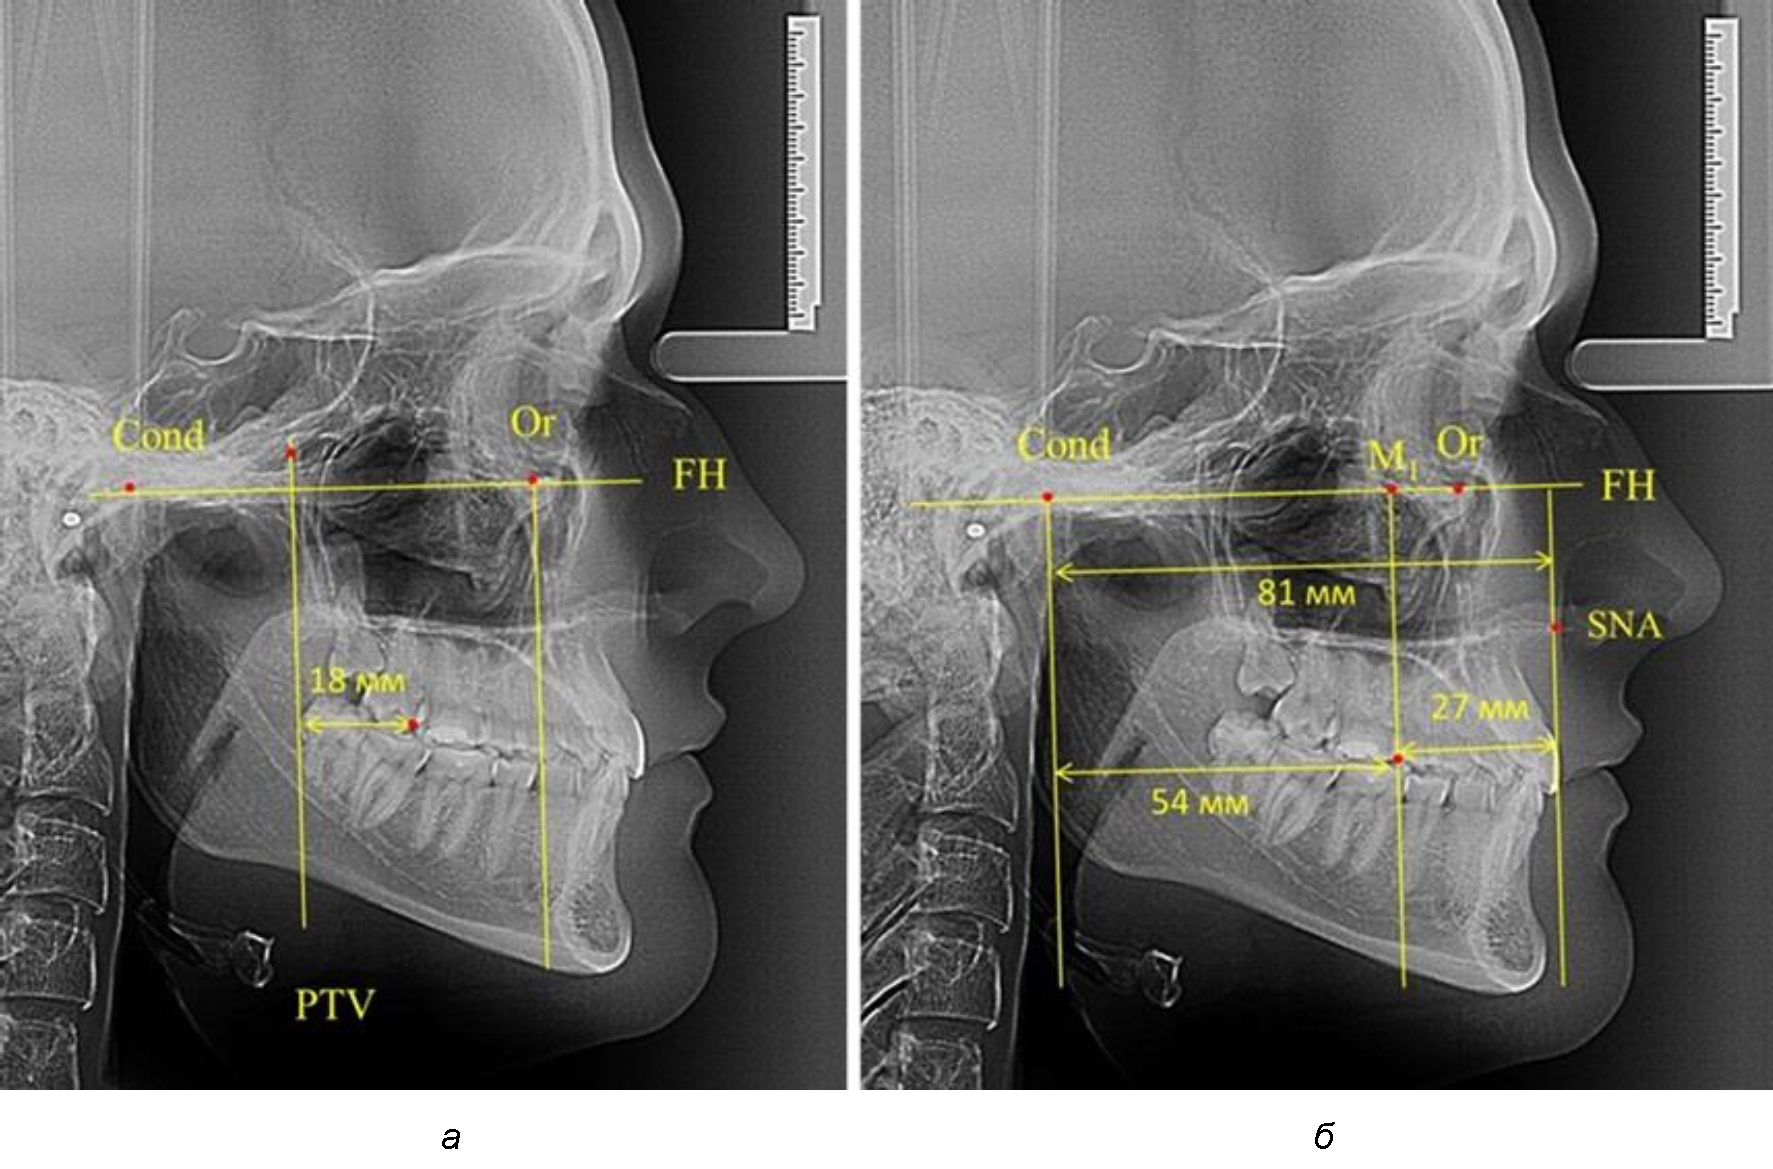

При проведении анализа к Франкфуртской горизонтали проводили передний и задний перпендикуляры. Передний спинальный перпендикуляр проходил через выступающую точку передней носовой ости (spina nasalis anterior – SNA), а задний суставной перпендикуляр опускали из кондилярной точки Cond. Молярный перпендикуляр проводили через медиальную поверхность первого постоянного моляра. Указанная вертикаль отделяла замещающие зубы постоянного прикуса от добавочных зубов (постоянных моляров), что вполне логично для анализа положения первых постоянных моляров в гнатическом комплексе (рис. 1).

Рис. 1. Метод определения положения первых верхних моляров по Ralph E. McDonald (а) и по предложенному методу (б)

Анализ проведенного исследования рентгенограмм показал существенную вариабельность практически всех линейных показателей. У молодых людей с физиологическим прикусом постоянных зубов расстояние от крыловидной вертикальной плоскости PTV до дистальной поверхности верхнего первого постоянного моляра в целом по группе составляло (18,37 ± 3,62) мм. Обращает на себя внимание большая ошибка репрезентативности из-за разницы между максимальными и минимальными значениями.

Среди анализируемых рентгенограмм минимальное значение расстояния по методу R. E. McDonald было 12 мм, а максимальное достигало 25 мм, что, по нашему мнению, обусловлено вариабельностью сагиттального размера гнатического отдела лица.